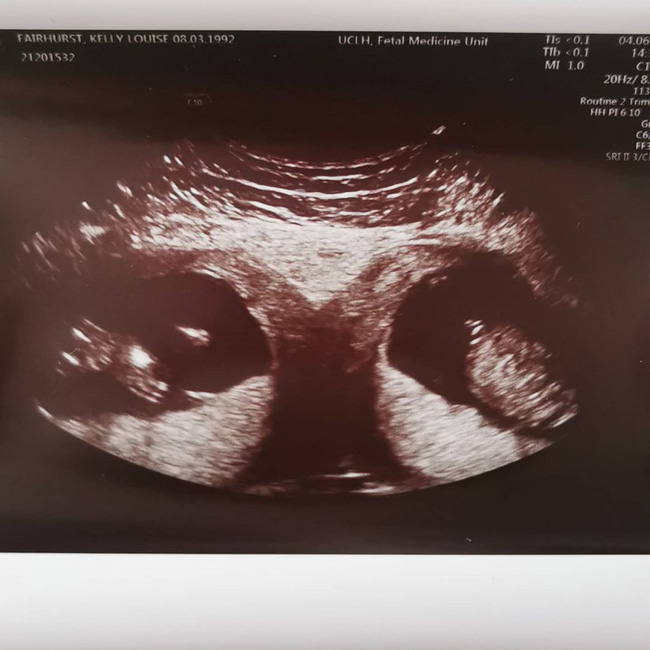

Kelly Fairhurst, một bà mẹ 28 tuổi ở Anh đã có 2 con gái, một bé lên 3 và một bé lên 4. Kelly hiện đang mang thai đôi nhưng điều đáng nói là cô phát hiện ra rằng mình có 2 tử cung riêng biệt hay tử cung kép (uterus didelphys) khi đi siêu âm ở tuần thứ 12. "Cặp song sinh có thể giống hệt nhau. Tình trạng này khá hiếm gặp, họ nói với tôi là tỉ lệ cho việc thụ thai song sinh trong hai tử cung khác nhau là 1/50 triệu", Kelly chia sẻ.

Bà mẹ này cũng cho biết thêm: "Khi sinh đứa trẻ thứ 2, bác sĩ đã nói tử cung của tôi có thể là tử cung hai sừng (bicornuate uterus), nghĩa là nó không được hình thành đầy đủ. Vì vậy khi đi siêu âm, tôi rất ngạc nhiên khi biết có 2 tử cung. Tôi chỉ nghĩ: 'Ơn Chúa, đó là một cú sốc'. Tôi cảm thấy vô cùng biết ơn vì điều này xảy ra với tôi và tôi có hai đứa con tuyệt vời". Bạn trai của Kelly là Joshua Boundy (34 tuổi) cũng đã không thể giấu nổi niềm hạnh phúc sung sướng khi biết tin.

Hiện tại, Kelly đã mang bầu được 19 tuần và 2 thai nhi vẫn đang rất khỏe mạnh. Cặp đôi đang háo hức chờ đến ngày biết được giới tính của các con.